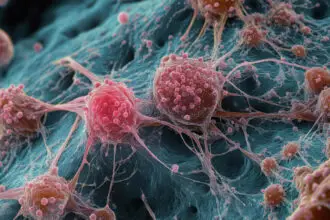

Diferentemente da gripe e resfriado, causados por vírus, a tuberculose é uma doença infecciosa provocada pela bactéria Mycobacterium tuberculosis, também conhecida como bacilo de Koch. A transmissão ocorre, como na maior parte das viroses, pelo ar, por meio da tosse, fala ou espirro de pessoas infectadas, com maior risco em ambientes fechados e pouco ventilados.